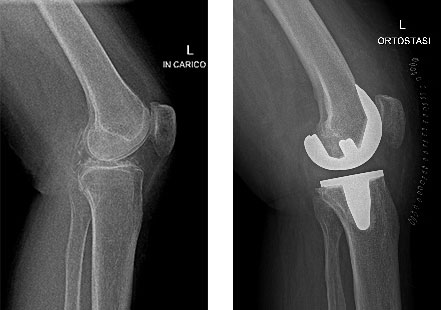

Paziente donna di 67 anni, affetta da gonartrosi tricompartimentale sinistra aggravata da calcificazione dei menischi, trattata con protesi totale mini invasiva del ginocchio a conservazione del legamento crociato posteriore.